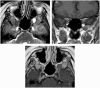

Intracranial trigeminal schwannomas are rare tumors. Patients usually present with symptoms of trigeminal nerve dysfunction, the most common symptom being facial pain. MRI is the imaging modality of choice and is usually diagnostic in the appropriate clinical setting. The thin T2-weighted CISS 3D axial sequence is important for proper assessment of the cisternal segment of the nerve. They are usually hypointense on T1, hyperintense on T2 with avid enhancement post gadolinium. CT scan is supplementary to MRI, particularly for tumors located in the skull base. Imaging plays a role in diagnosis and surgical planning. In this pictorial essay, we retrospectively reviewed imaging findings in nine patients with pathologically proven trigeminal schwannoma. Familiarity with the imaging findings of intracranial trigeminal schwannoma may help to diagnose this entity.